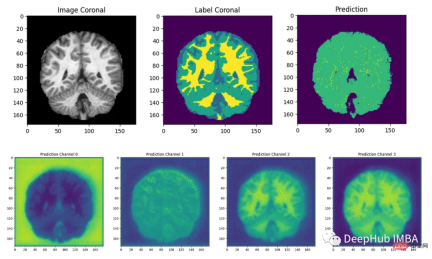

结果分析

最后我们要看看模型是如何推广到未知数据的这个模型预测的几乎所有东西都是左脑白质,一些像素是左脑皮层。尽管它的预测似乎是正确的,但仍有很大的改进空间,因为我们的模型太小了,可以选择更深的模型获得更好的效果。